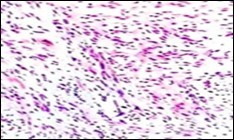

Figure 2.Soft tissue perineurioma with lamellar bundles of neural cells demonstrating elongated cytoplasmic processes, wavy, slender nuclei and admixed collagen fibres 12.

Soft tissue perineurioma with lamellar bundles of neural cells demonstrating elongated cytoplasmic processes, wavy,  slender nuclei and admixed collagen fibres 12.